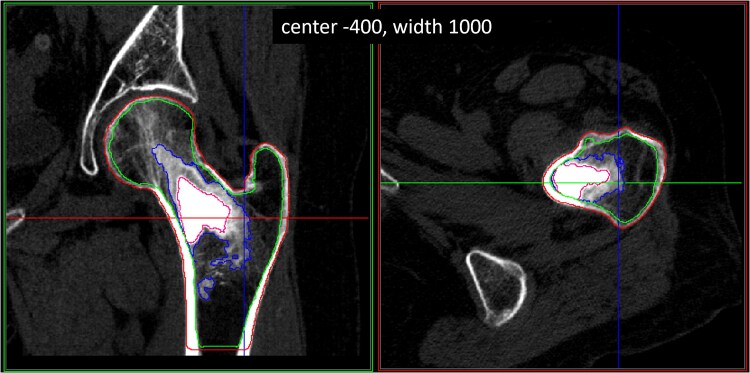

在这项研究中,QCT用于分析AGN1局部骨增强手术(LOEP)作为骨质疏松症患者股骨近端成骨的治疗方法。使用这种微创手术,将可吸收的三相AGN1植入材料注射到12名绝经后骨质疏松症妇女的左股骨中。在治疗前(基线)、治疗后12周、24周和5-7年进行计算机断层扫描。定量计算机断层扫描用于研究AGN1在治疗的股骨近端内的吸收,并分析治疗对整体骨、小梁骨和皮质骨的影响。未治疗的右侧股骨作为对照。数据显示,治疗后的髋部在所有时间点(基线:22±21 mg/cm3 vs 217±56 mg/cm3, 161±18 mg/cm3和121±37 mg/cm3分别在12周,24周和5至7年时间点)的骨小梁体积骨密度(trab vBMD)增加,整体vBMD在12周时间点增加65%,在5至7年时间点增加34%。在注射AGN1植入材料丸的位置观察到trab vBMD增加,在5- 7年的时间点上,在原始植入区域周围的小梁区域未观察到明显的BMD变化(治疗组:32±16 mg/cm3,对照组:31±16 mg/cm3)。本QCT研究更详细地了解了AGN1植入材料在骨中的吸收和转化,并支持AGN1 LOEP治疗可以局部增加股骨近端薄弱区域的骨小梁密度,在该区域最需要增加强度以降低髋部脆性骨折的风险,但存在一定局限性。

In this study, QCT was used to analyze the AGN1 Local Osteo-Enhancement Procedure (LOEP) as a treatment to form bone in the proximal femurs of patients with osteoporosis. Using this minimally invasive procedure, a resorbable triphasic AGN1 implant material was injected into the left femurs of 12 women with post-menopausal osteoporosis. Computed tomography scans were taken before treatment (baseline) and at 12 wk, 24 wk, and 5-7 yr after treatment. Quantitative computed tomography was used to investigate the resorption of AGN1 within the treated proximal femurs and to analyze the treatment's impact on integral, trabecular, and cortical bone. The untreated right femurs were used as controls. Data illustrated an increase in trabecular volumetric BMD (trab vBMD) of treated hips at all timepoints (baseline: 22 ± 21 mg/cm3 vs 217 ± 56 mg/cm3, 161 ± 18 mg/cm3, and 121 ± 37 mg/cm3 at 12-wk, 24-wk, and 5- to 7-yr timepoints, respectively), and an increase in integral vBMD of 65% at the 12-wk timepoint and 34% at the 5- to 7-yr timepoint. The increase in trab vBMD was observed in the location where the AGN1 implant material bolus was injected, and at the 5- to 7-yr timepoint, no significant BMD change was observed in the trabecular regions surrounding the original implantation zone (treated: 32 ± 16 mg/cm3, control: 31 ± 16 mg/cm3). This QCT study provides a more detailed understanding of the resorption and transformation of the AGN1 implant material into bone and supports, with some limitations, that the AGN1 LOEP treatment can locally increase trabecular bone density in weakened areas of the proximal femur where strength increase is most needed to reduce the risk of hip fragility fracture.